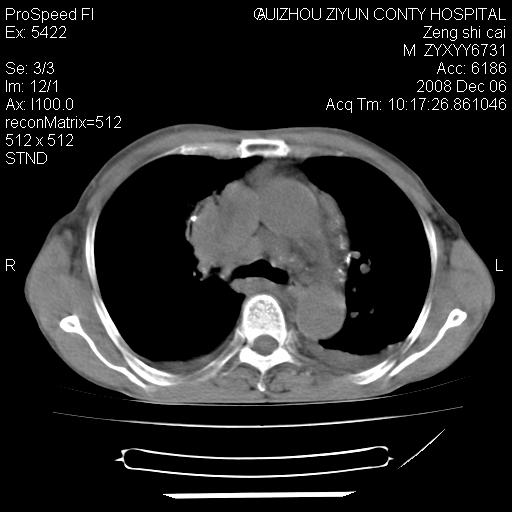

标题: CT16961:M、71岁,咳嗽半年,无血痰;胸片示右肺占位。 [打印本页]

标题: CT16961:M、71岁,咳嗽半年,无血痰;胸片示右肺占位。

1)考虑右肺上叶纵隔型肺癌伴纵隔淋巴结转移。2)心包积液,双侧胸腔积液。

右肺癌并纵隔淋巴转移,腹膜后转移可能性大,两侧胸腔积液

右肺上叶纵隔型肺癌伴纵隔淋巴结转移。心包积液,双侧胸腔积液。